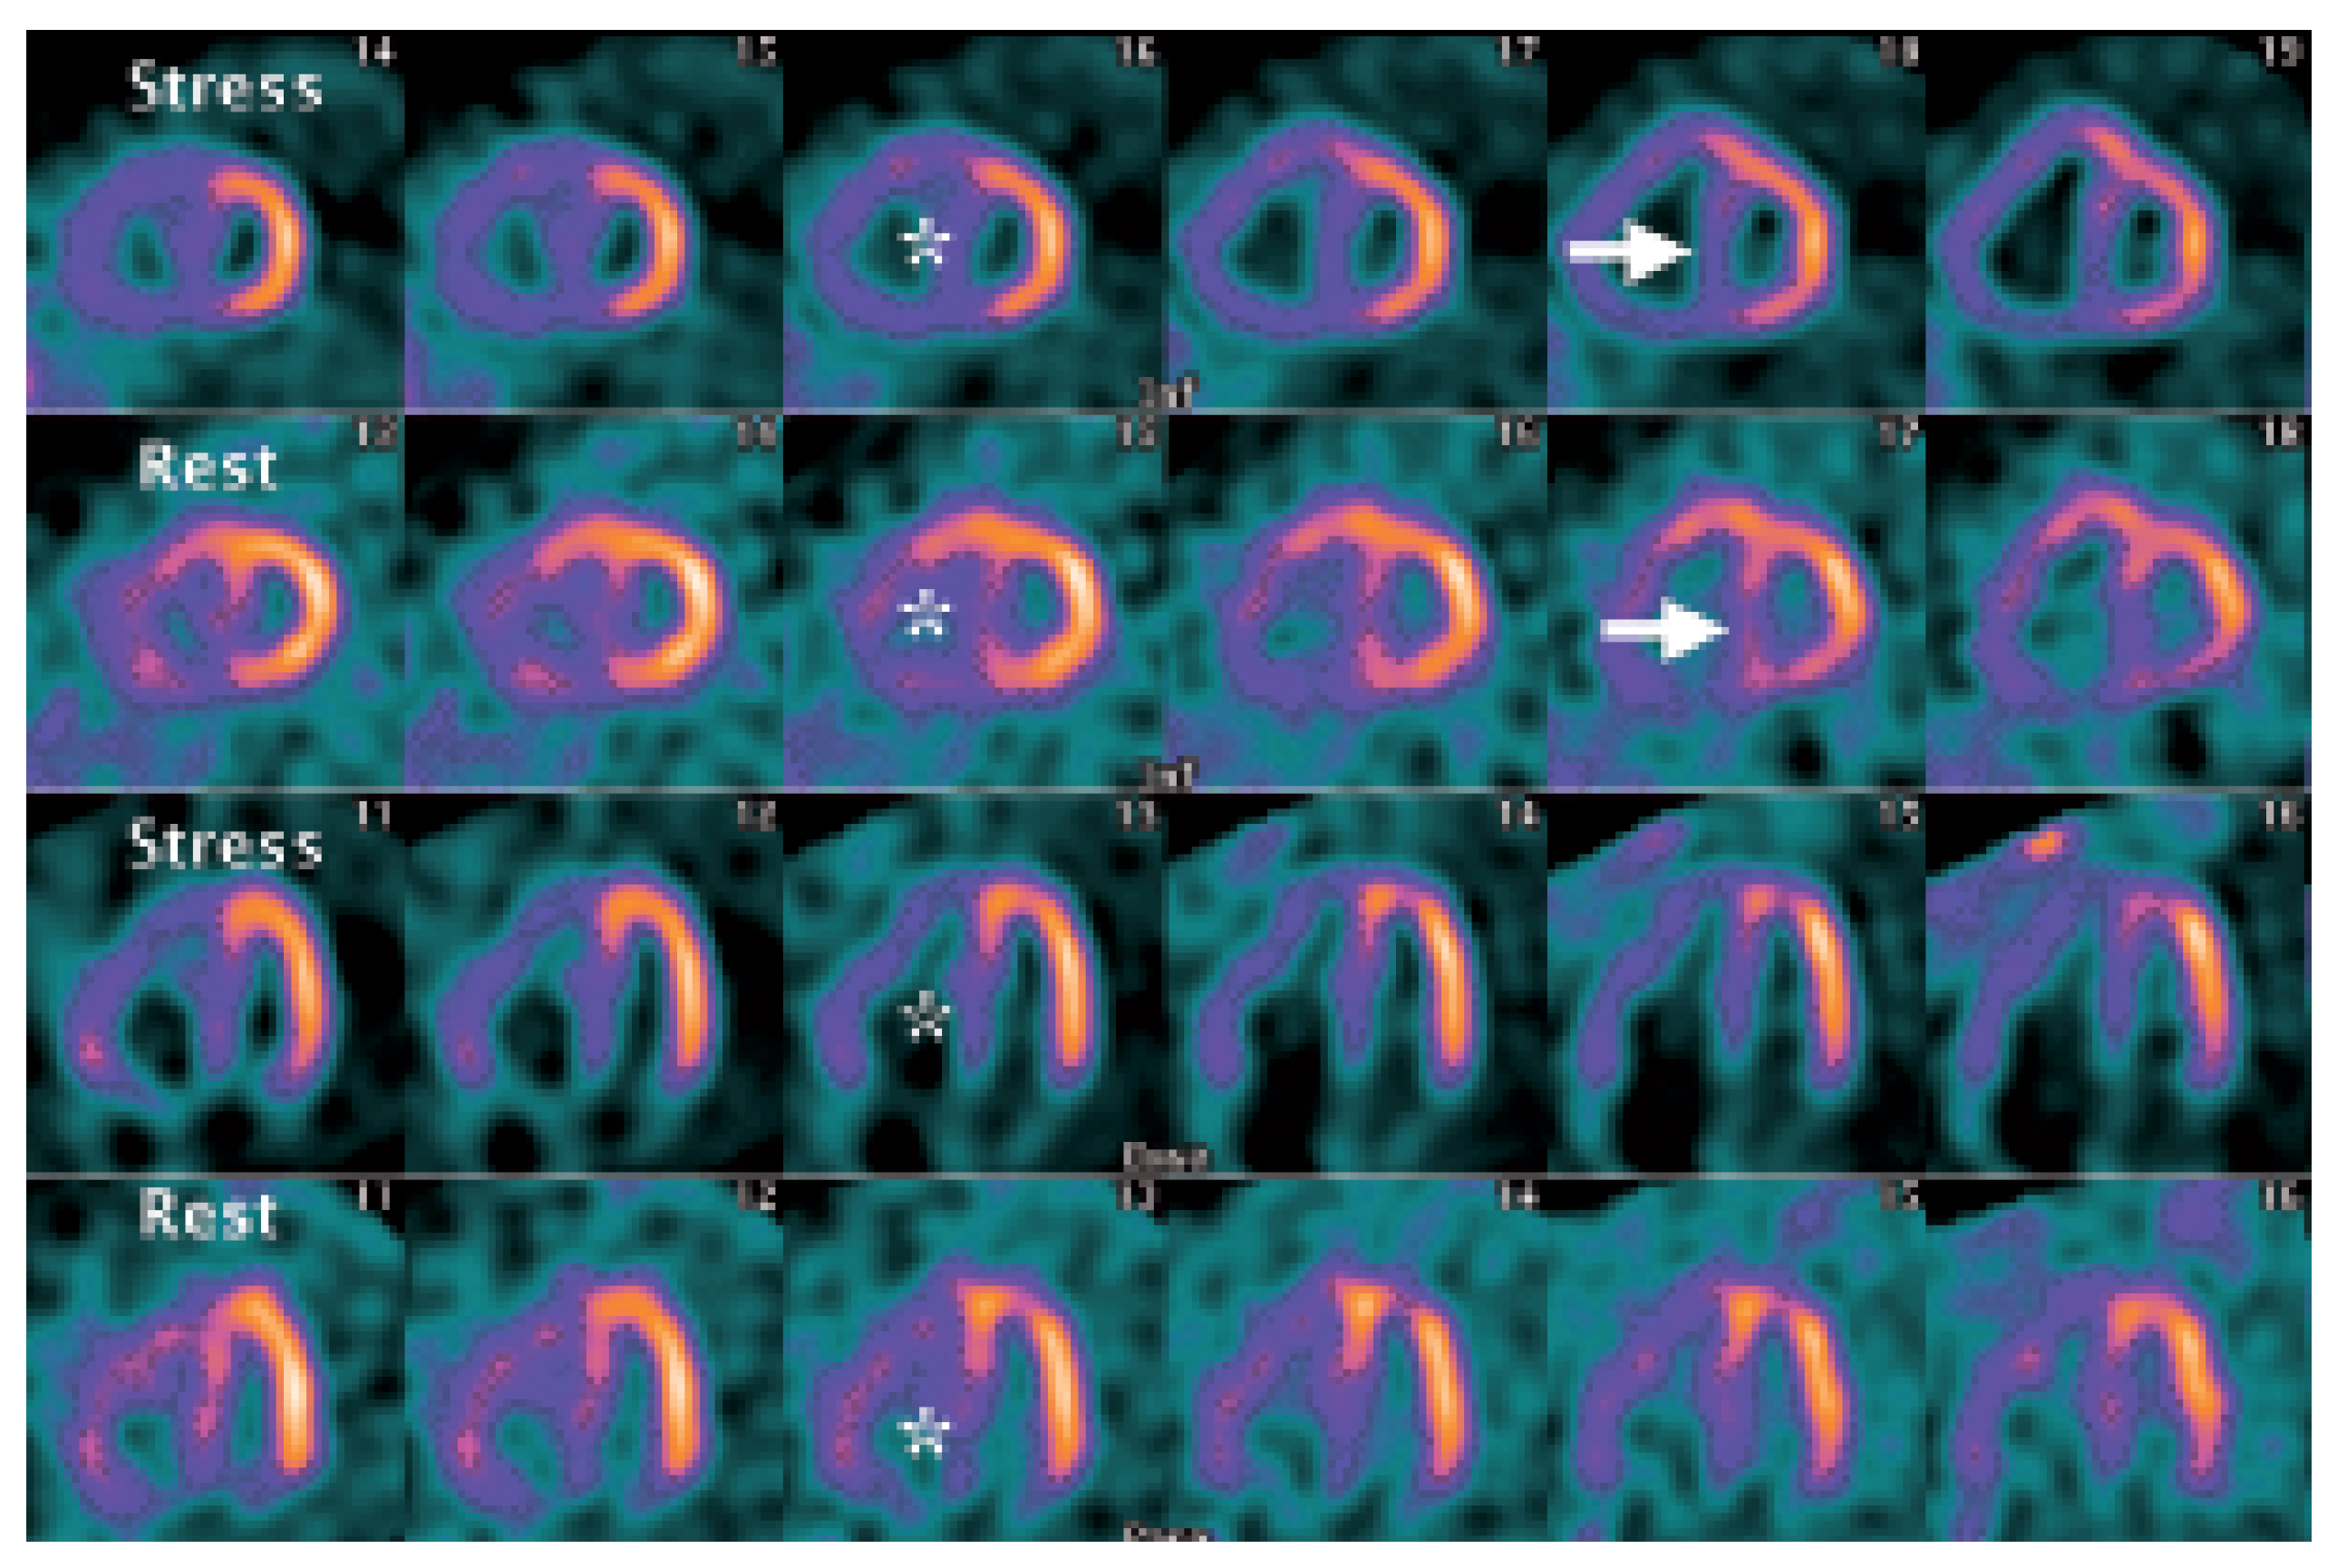

Myocardial Perfusion SPECT Features of Severe Pulmonary Artery Hypertension

Case Report